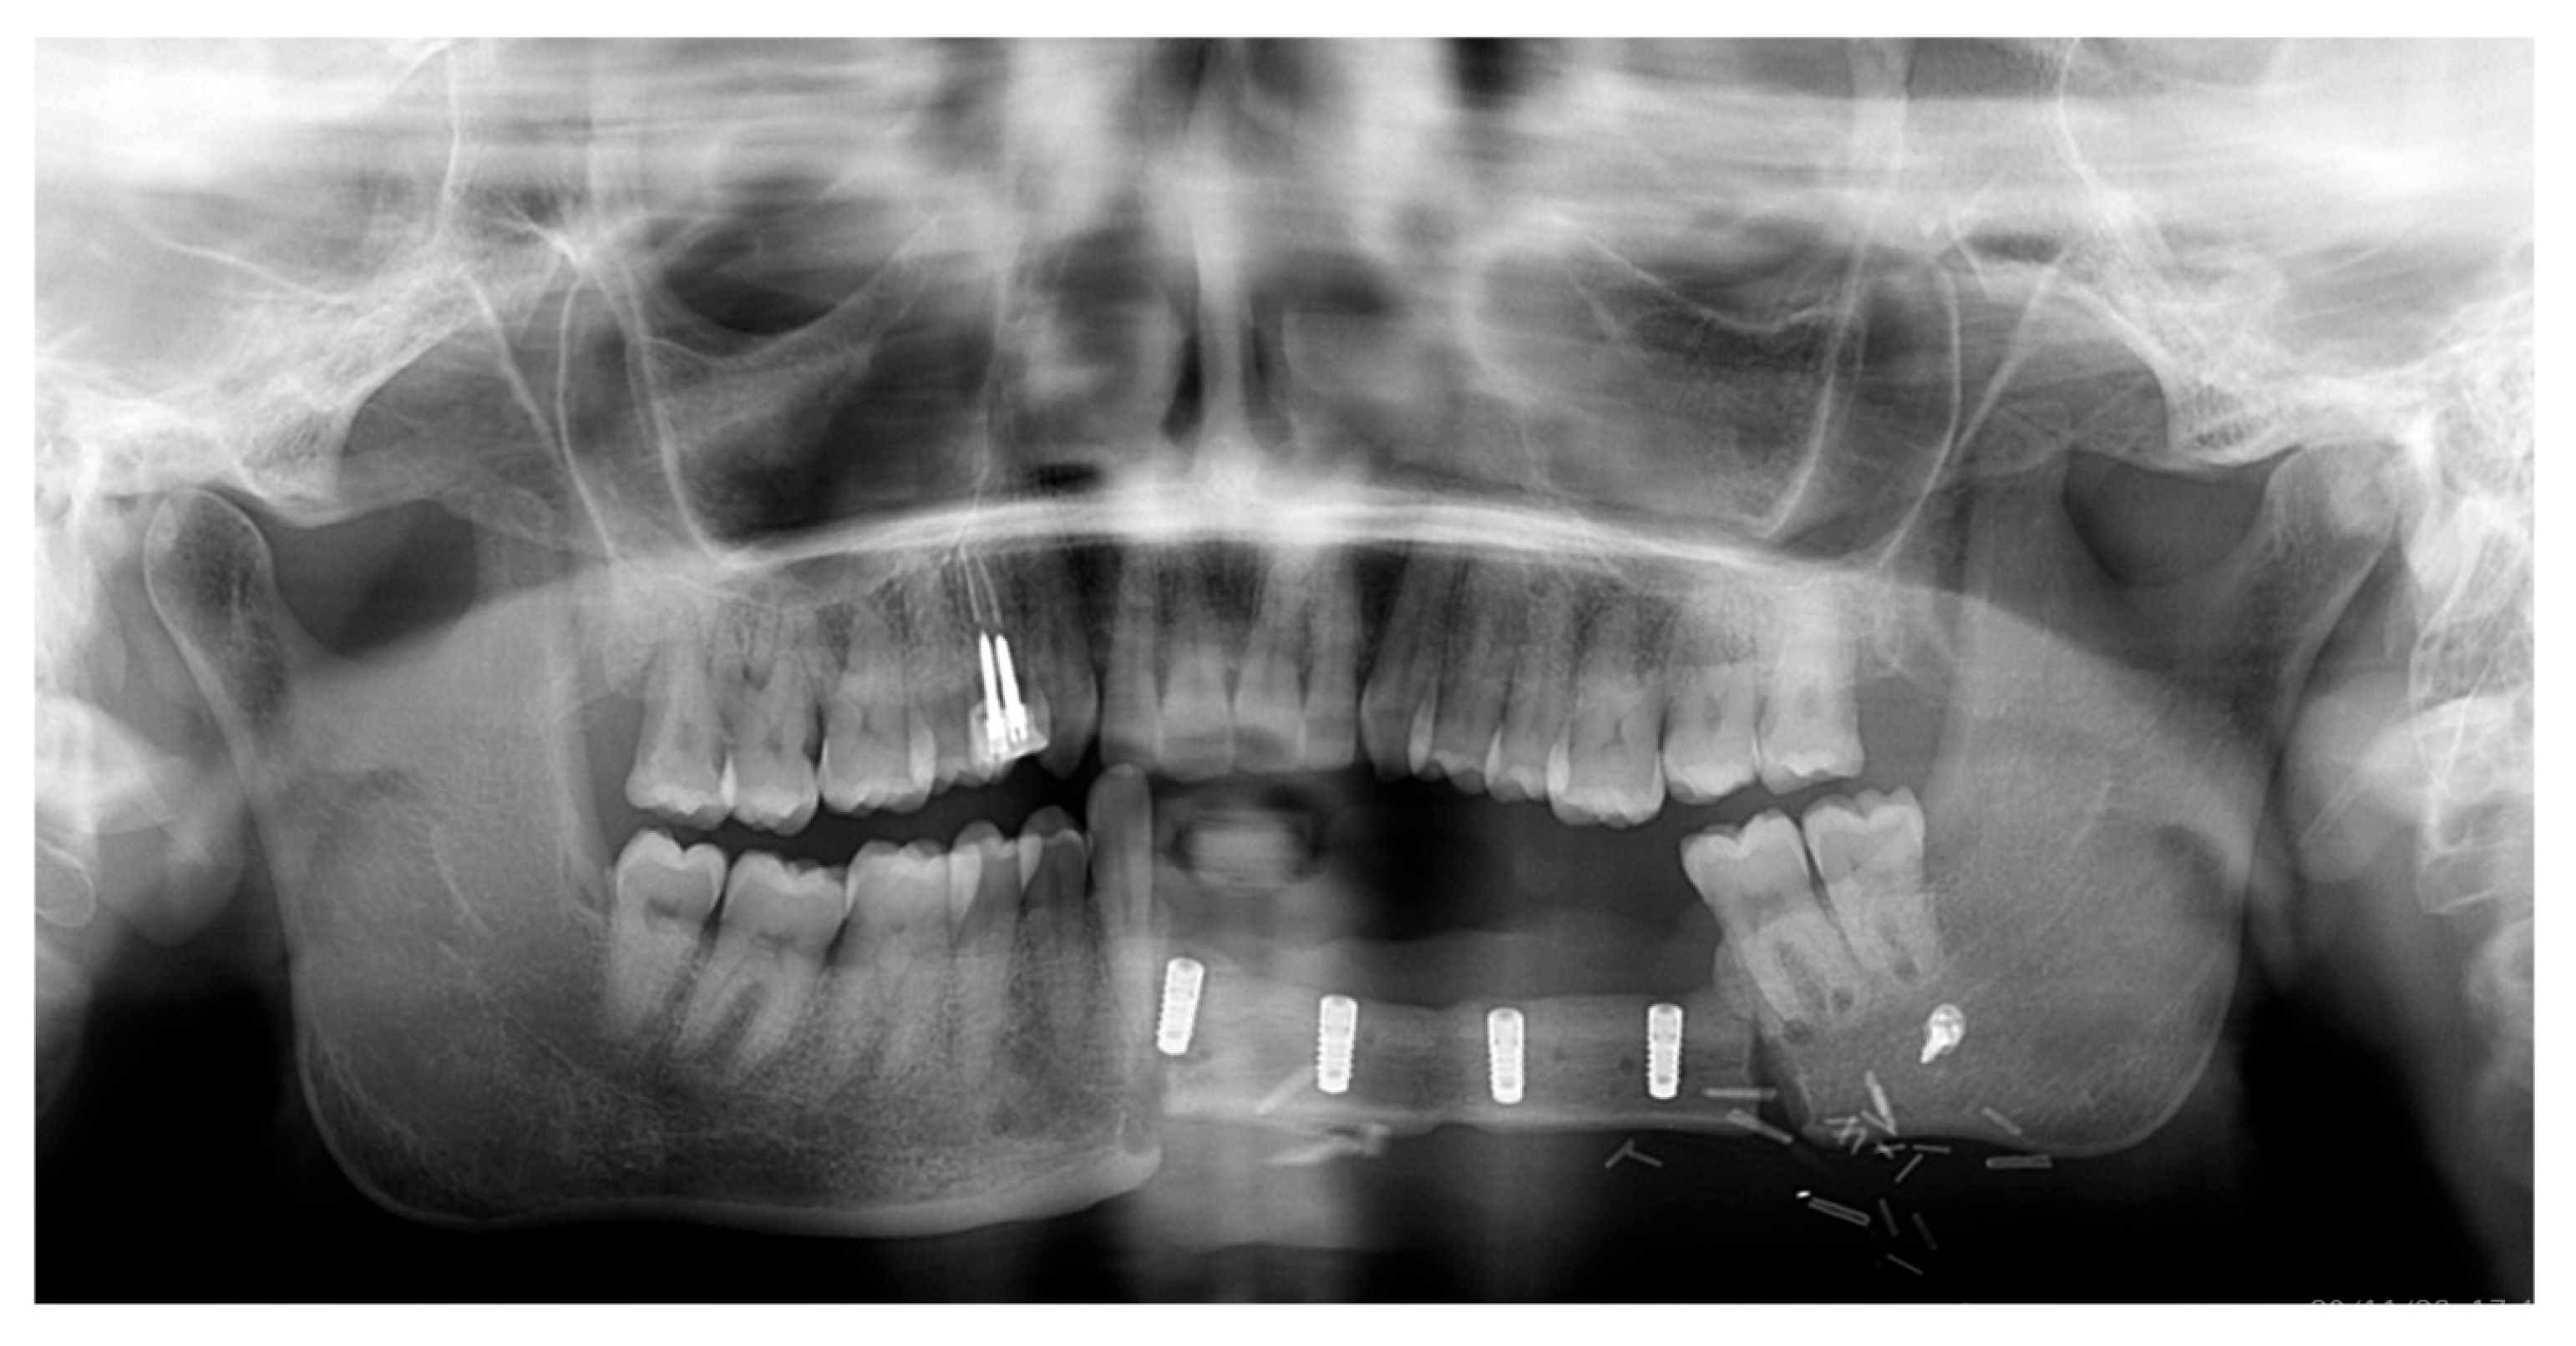

After a 3-month healing period, an OPG was performed, and implant uncovering and soft tissue surgery were planned (Figure 6).

Figure 6.

Postoperative OPG.

During the second surgery, one implant exhibited absence of osseointegration with no signs of infection and was then removed. Notably, this implant was located near the transition zone between the remaining mandibular bone and the fibula graft, which may have contributed to its failure due to reduced vascularization [21]. An internal connection with a screw-retained abutment was chosen for the prosthetic rehabilitation. Multi-unit abutments (MUAs) were employed to optimize load distribution among the implants. Three MUAs and healing caps were placed, and the flap was apically repositioned to improve buccal fornix depth. The two mesial MUAs had a height of 3.5 mm, whereas the distal one measured 5.5 mm.

The prosthetic rehabilitation was completed four months after implant placement using a bar-retained, metal reinforced resin overdenture. Due to an unfavorable crown-to-root ratio and the loss of one implant, a removable prosthesis was selected—following discussion with the patient—to avoid overloading the remaining implants and to achieve a more favorable distribution of occlusal forces [22]. Furthermore, the decision was supported by the improved ease of oral hygiene maintenance associated with a removable prosthesis.

Analogic impressions were taken with the use of polyether impression material. Performing this prosthetic rehabilitation was challenging because taking impressions on the implants was difficult due to the patient’s limited mouth opening, as the muscles had been cut during the reconstructive surgery of the mandible. With the prosthesis, restoration of masticatory function and improvement in facial aesthetics were observed. The patient experienced a positive impact on her self-esteem and social interactions (Figure 7).

Figure 7.

Clinical (A,B) and radiographic (C) situation after prosthetic delivery.

Patient satisfaction was evaluated using a Visual Analogue Scale (VAS) ranging from 0 to 10, assessing both aesthetic and functional outcomes. The patient reported the highest possible score—10 in both categories—indicating maximum satisfaction. Overall, the patient expressed a high level of satisfaction with the treatment outcomes.